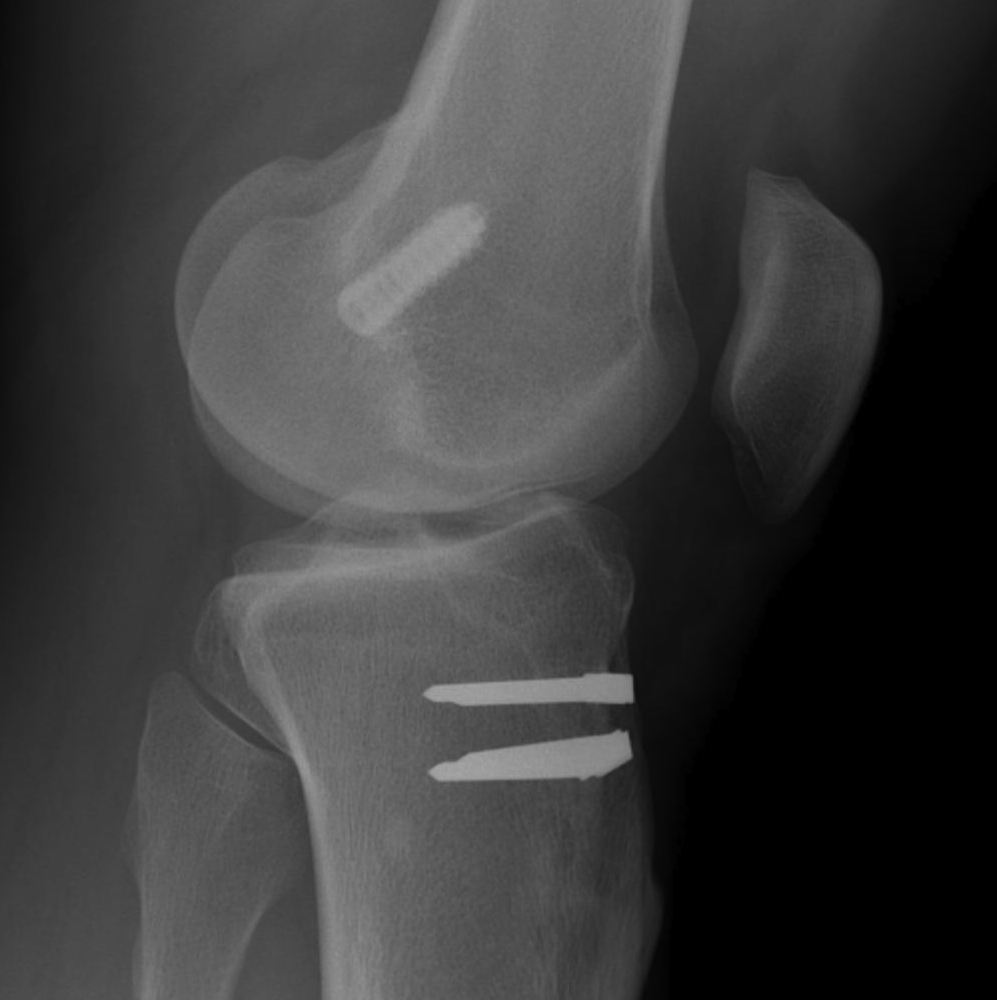

D. Graft Fixation Failure

Takes 6-12 weeks for graft incorporation to occur with hamstrings

Graft fixation needs to be strong for this period

E. Tunnel Lysis

Very common, cause unknown

No evidence that contributes to instability

Important in revision setting

Cause

- more common tibial side than femur

- tends to stop after 3/12

- postulated to be from synovial fluid pistoning

- hence fluid finds it easier to come down tibial tunnel as screw placed outside in

- also seen more on femoral side with endobutton (windscreen wiper effect)